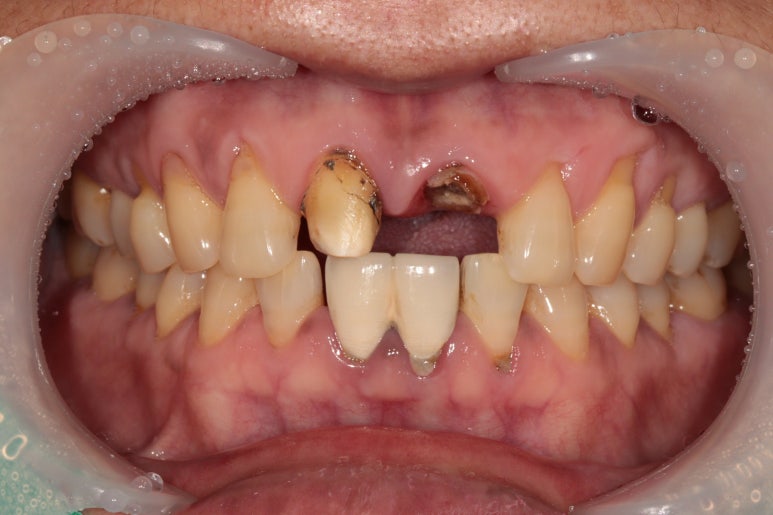

앞니 보철물이 빠져서 내원하시게 되신 환자분의 케이스입니다.

타원에서 치료받으신 보철물을 그동안 잘 사용하고 있었는데,

어제 갑자기 윗니 쪽으로 가벼운 충격이 있었고,

바로 보철물이 빠지셨다고 합니다.

2024. 1 기존의 보철물은 위 앞니 두 개를 연결한 형태였다고 하시네요.

환자분의 현재 상태를 보고 원인을 유추해 보았습니다.

기존에 연결된 앞니 보철물과 치아의 경계부 사이로 2차 충치가 진행이 오랜 기간 지속되었고,

보철물 내부의 치아에 충치가 심해져 약해져 있던 상태에서

작은 충격에 그 보철물이 빠져버리게 된 것입니다.